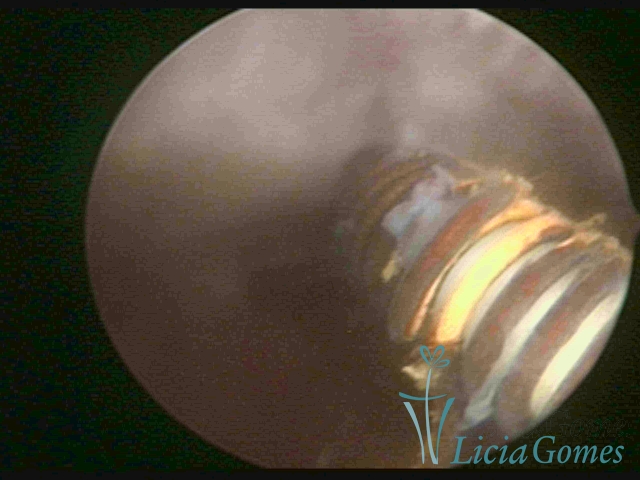

Myometrium punctured IUD

IUD distal extremity